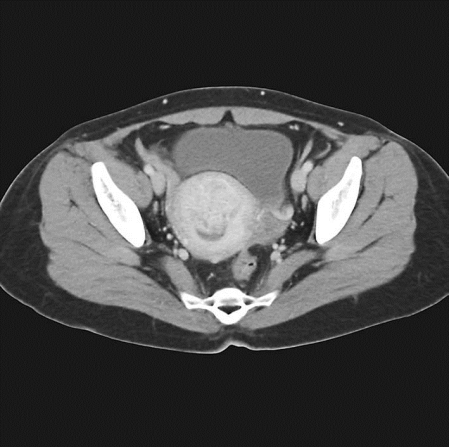

子宫腺肌病MR